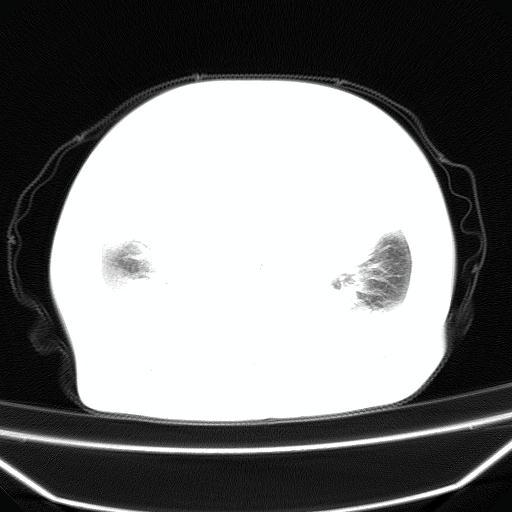

以下是引用jiangjing在2008-4-20 10:43:00的发言:[br]结合病史支持 冠心病[冠状动脉钙化],心功能不全,肺淤血、肺水肿,双侧胸腔与斜裂积液

以下是引用liuyue在2008-4-19 22:25:00的发言:[br]先考虑:1.心衰伴肺水肿、双侧胸腔积液、叶间积液、双下肺不完全性肺不张; [br] 2.冠状动脉粥样硬化。

以下是引用lijuanln在2008-4-19 23:05:00的发言:[br]两侧胸腔积液,肺水肿[br]心包积液[br]提示心衰